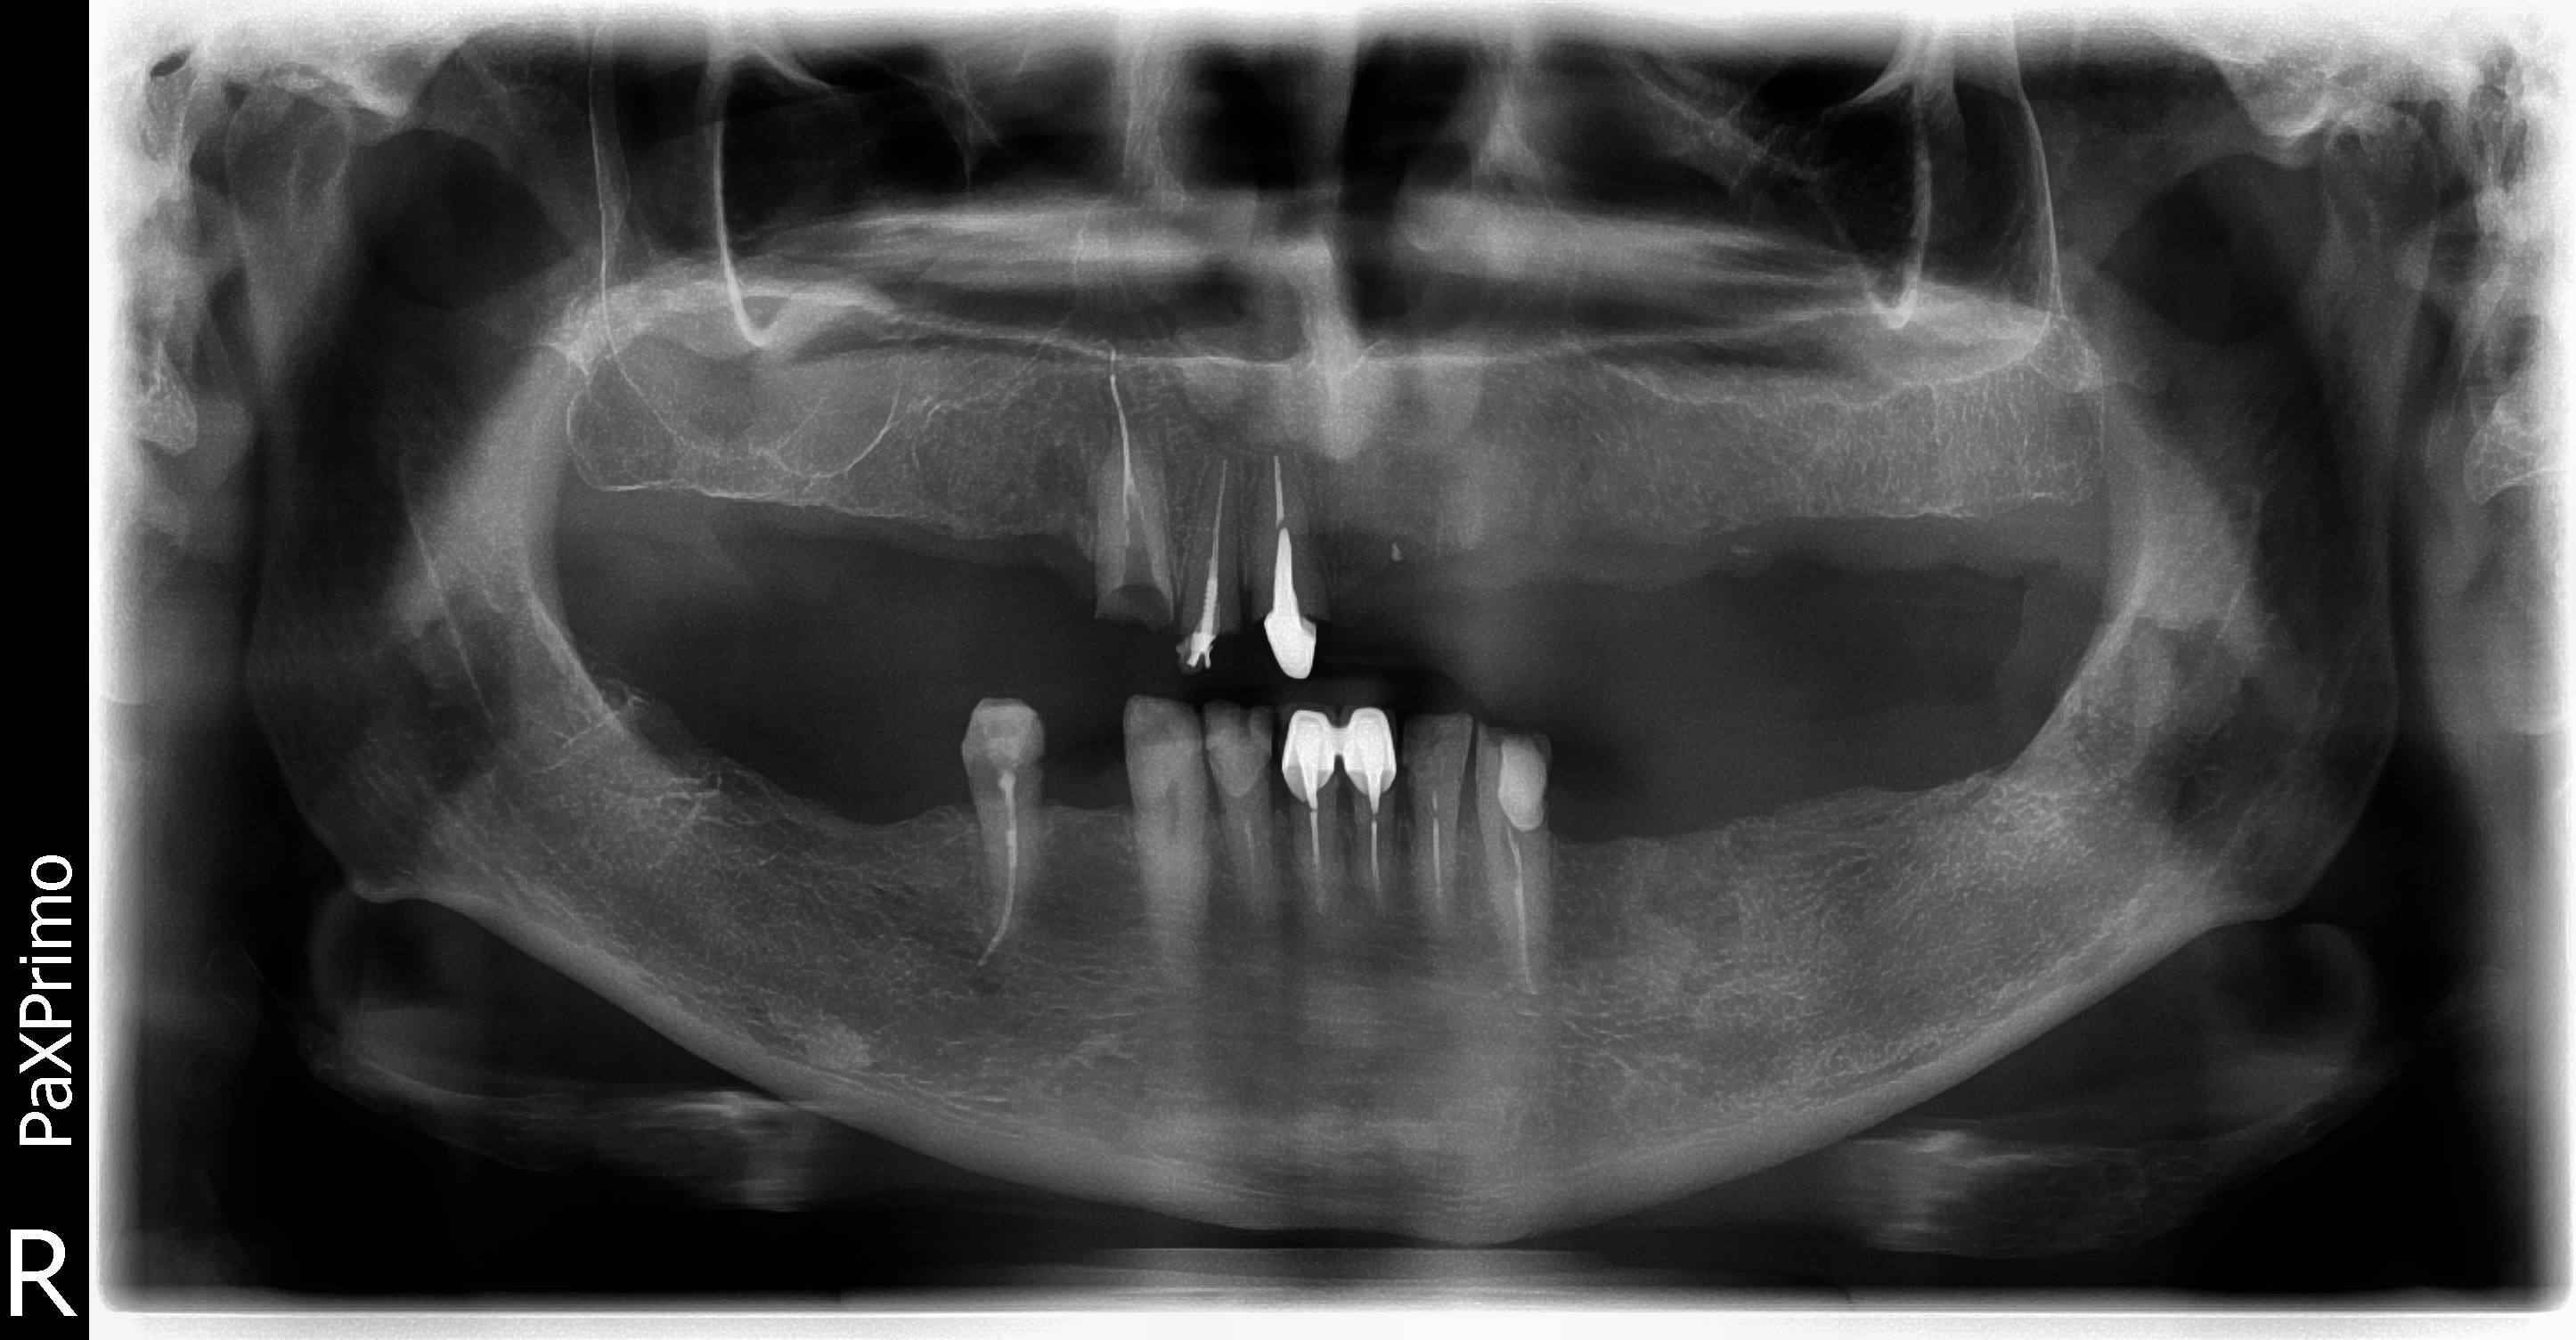

Стоматологические Исследования: Рентген Инвагинации Зубов